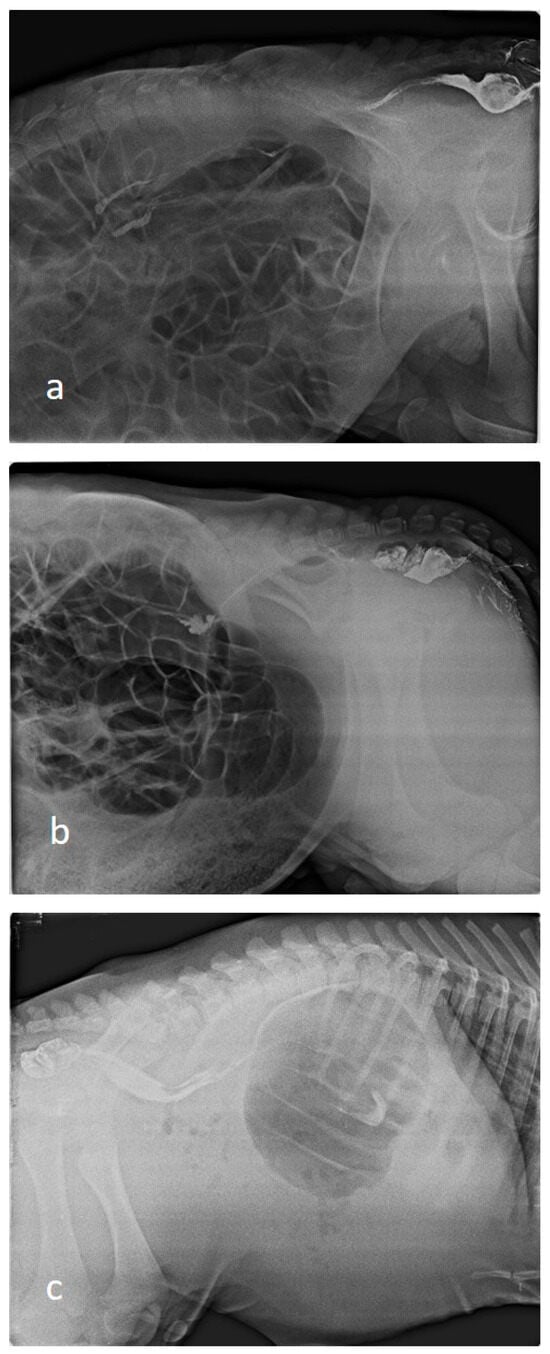

Indirect radiography was performed in all calves by rectal administration of barium sulphate contrast agent. Barium sulphate (E-Z-HD Barium sulphate, 98% powder, 340 g, OPAKIM, İstanbul, Türkiye) was diluted 1:3 with water and administered at a dose of 1 mL/kg via rectal probe [30]. The blind ends of the colon or rectum were radiographically visualised after barium administration (Figure 1). Barium-contrast radiography also showed the blind part of the colon. Indirect radiography was performed in the latero-lateral position using a 70 kilovolt (kV) and 150 milliampere (mA) setting on an X-ray machine (BLD-150AJ, AJEX Meditech Ltd., Seoul, Republic of Korea) with Fujifilm Computed Radiography (CR-IR 392, Fujifilm, Shanghai, China).

3.4. Radiographic Findings

In cases of atresia coli, radiographic evaluation revealed that the intestinal passage terminated in a distal segment, resulting in severe proximal distension. In abdominal radiographs of calves, it was observed that the spiral colon and cecum were markedly distended with gas and liquid content, whereas distal colonic segments were free of gas and content. An enlarged gas-filled intestinal anus, especially in the left flank region, was typical. Contrast-enhanced radiography revealed that the contrast had travelled up to a certain level, and no passage distal to the atretic segment was observed.

Figure 1. Indirect radiographic images of calves ((a); Type I, (b,c); Type III).